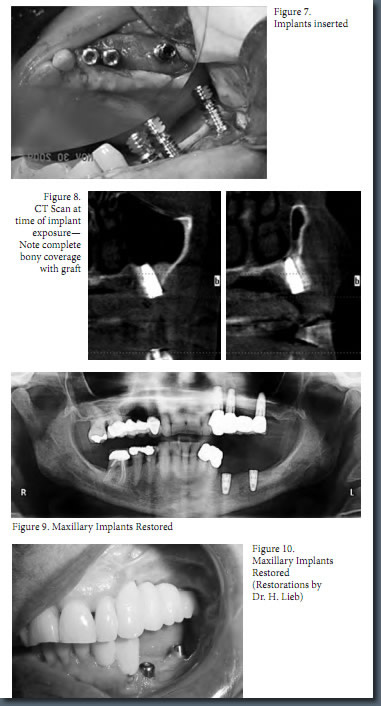

Mark Stein, D.D.S., M.D. of New York Oral and Maxillofacial Surgery Dental Implant Center was recently published in New York County Dental Society's 18th volume of Dentists’ Quarterly for his article on the newest technology available to help bone grafting and dental implants, the recombinant human bone morphogenetic protein in New York City. Dr. Stein’s article, “A New Approach to Reconstructing Difficult Maxillary Defect— Recombinant Human Bone Morphogenic Protein,” depicts an easier, less invasive, safer, and more efficient method of gaining enough bone support to anchor dental implants. Bone Morphogenic Protein (BMP) in NYC actually stimulates bone formation at the site in need of more bone support, circumventing the need for bone grafts in order to insert dental implants.

According to Mark Stein, D.D.S., M.D., dental professionals are leaning away from removable dentures and towards permanent dental implants as the first method of choice in order to repair missing teeth. Some patients, however, lack the necessary bone density to make dental implants a viable option. Until recently, bone grafting in NY was the standard procedure to improve a person’s bone density and prepare their jaw for dental implants in NY. Bone grafting, however, involves harvesting bone from a donor location, such as another location on the mouth or the hip, and transferring the harvested bone to the jaw. After bone grafting, patients must wait 4 to 9 months for the grafting site to heal before they may receive implants. This process was necessary to enhance bone density and was the only means to achieve more bone tissue in the needed area. With the advent of bone morphogenic protein in NY, oral surgeons, such as Mark Stein, D.D.S., M.D., can achieve more bone in the needed area by stimulating the bone itself to produce more bone cells.

Recombinant human bone morphogenetic protein Bone Graft in New York City is comprised of two active ingredients: a manmade protein found naturally in the body and an absorbable collagen sponge (ACS). The protein stimulates the formation of new bone, and the absorbable collagen sponge regulates when the protein is released over a period of time. The absorbable collagen sponge also acts as a trellis on which the newly stimulated bone may form, grow, and take shape. Eventually, the body absorbs the ACS with actual bone. Using bone morphogenic protein in NY instead of traditional bone grafting in New York to increase bone density completely eliminates the need for donor bone from a donor site. This method provides patients with an easier, less invasive procedure to ready the mouth for dental implants in New York.

Do view Dr. Stein’s complete article, click on the following title: A New Approach to Reconstructing Difficult Maxillary Defect— Recombinant Human Bone Morphogenic Protein.